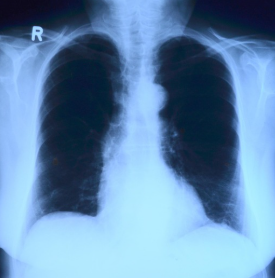

폐기흉(기흉)이란 무엇인가?

폐기흉은 폐의 공기주머니(폐포)가 터지면서 공기가 흉막강으로 새어 나와, 폐가 수축되는 질환입니다.

정상적으로는 폐가 공기를 들이마시고 내쉬면서 팽창과 수축을 반복하지만, 흉강 내 압력이 높아지면 폐가 펴지지 못해 호흡 곤란을 유발합니다.

전유성 씨의 경우, 과거 폐렴 이력이 있었고 고령으로 인해 폐 기능이 약화된 상태에서 폐기흉이 치명적으로 작용한 것으로 추정됩니다.